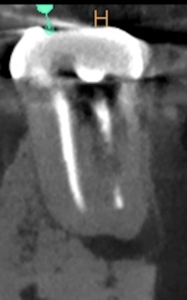

術後にPA, CBCTを撮影した。

#19 MB

#19 ML

#19 D

問題はないと思われる。